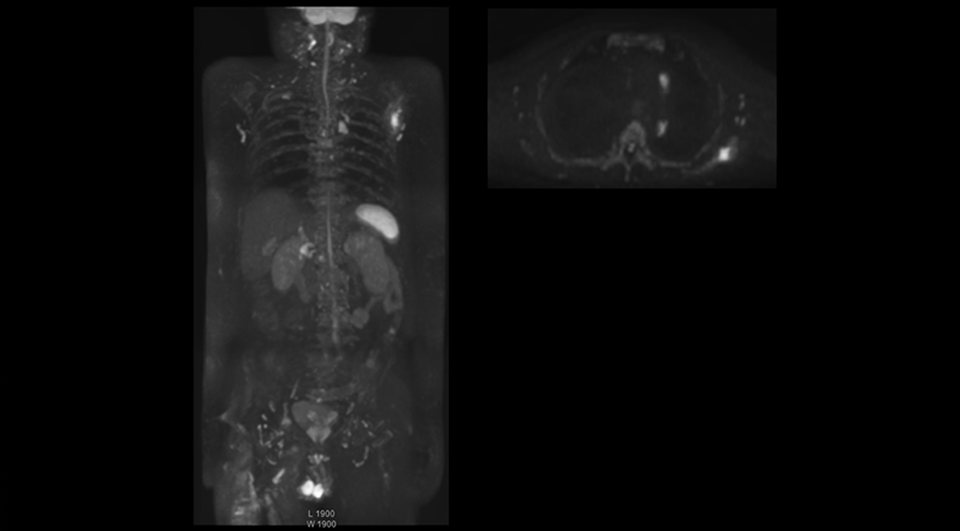

Radiologist Hiroshi Nobusawa, MD, PhD, explains that the coronal DWIBS protocol for whole body DWI is excellent for visualizing lesions in oncology patients. “About 90% of the DWIBS exams are done in this type of patients. The remainder of DWIBS exams are performed to gain information in cases of fevers of unknown origin,” he says. in image acquisition and postprocessing algorithms.”“mDIXON TSE sequences allow simultaneous characterization of morphological changes from the in-phase T2-weighted images and visualization of edematous changes, thanks to the water T2-weighted images from the same acquisition. Anatomical and morphological considerations could be a partial or complete ligament tear, a bony avulsion or hematoma.” “For soft tissue assessment mDIXON brings similar benefits. For example in one T2-weighted mDIXON TSE acquisition, having the multiple contrasts helps us assess abnormalities in peripheral nerves fascicles, which may be due to anatomical or inflammatory changes..” “In peripheral joints, we get good image quality in difficult areas with mDIXON TSE. Fat suppressed images appear homogeneous over the entire image, even with large coverage at 3.0T – for instance in scapular or hip girdles – or in the bearing areas or around metal prostheses*, where fat suppression is often deficient with STIR or spectral fat suppression, causing diagnostic difficulties. If a diagnostic image is right the first time, we don’t need to repeat or add a sequence.” “mDIXON TSE sequences allow simultaneous characterization of morphological changes from the in-phase T2-weighted images and visualization of edematous changes, thanks to the water T2-weighted images from the same acquisition. Anatomical and morphological considerations could be a partial or complete ligament tear, a bony avulsion or hematoma.” “For soft tissue assessment mDIXON brings similar benefits. For example in one T2-weighted mDIXON TSE acquisition, having the multiple contrasts helps us assess abnormalities in peripheral nerves fascicles, which may be due to anatomical or inflammatory changes..”

“The DWIBS sequence’s value in oncology cases is due to the high contrast it creates between lesions and surrounding tissue. Whole body DWI is requested by physicians who need to clarify TNM staging or determine therapeutic strategies, oncologists in need of diagnosis or follow-up scans, surgeons who need to see the presence of distant lesions that are sometimes difficult to detect by CT before surgery, and urologists for the evaluation of bone lesions, and the effect of chemotherapy and radiotherapy.”

After implementing the improved whole body protocol, the radiology team initially did not see a large increase in referrals, although Dr. Nobusawa saw clinical cases where the DWIBS images provided him valuable information for diagnosis. This is why Dr. Nobusawa and Mr. Naka started to actively educate referring physicians about the value of whole body DWIBS. They organized several presentations for physicians in the hospital, where they explained how DWIBS can be of value in oncology patients. The information it provides can be useful for physicians when staging cancer, as well as when determining or adjusting treatment strategy. Mr. Naka remembers some cases where DWIBS provided remarkable information. “In one example, DWIBS visualized bone lesions that could not be seen on PET or SPECT. In another case we had found a bone lesion when a normal L-spine scan for narrowing of the disk space was done. One extra DWIBS scan (2 stations, 8 minutes) demonstrated a lesion that later was confirmed to be the primary region of cancer.”

In certain cases, radiologists now choose DWIBS to make diagnoses that used to depend on nuclear medicine studies. “We don’t have SPECT or PET in our hospital, so for instance for visualizing metastasis and monitoring the effect of treatments such as chemotherapy or radiotherapy, we used to refer patients outside the hospital. Now, these patients are sent to MRI for our whole body protocol with DWIBS,” Mr. Naka says.